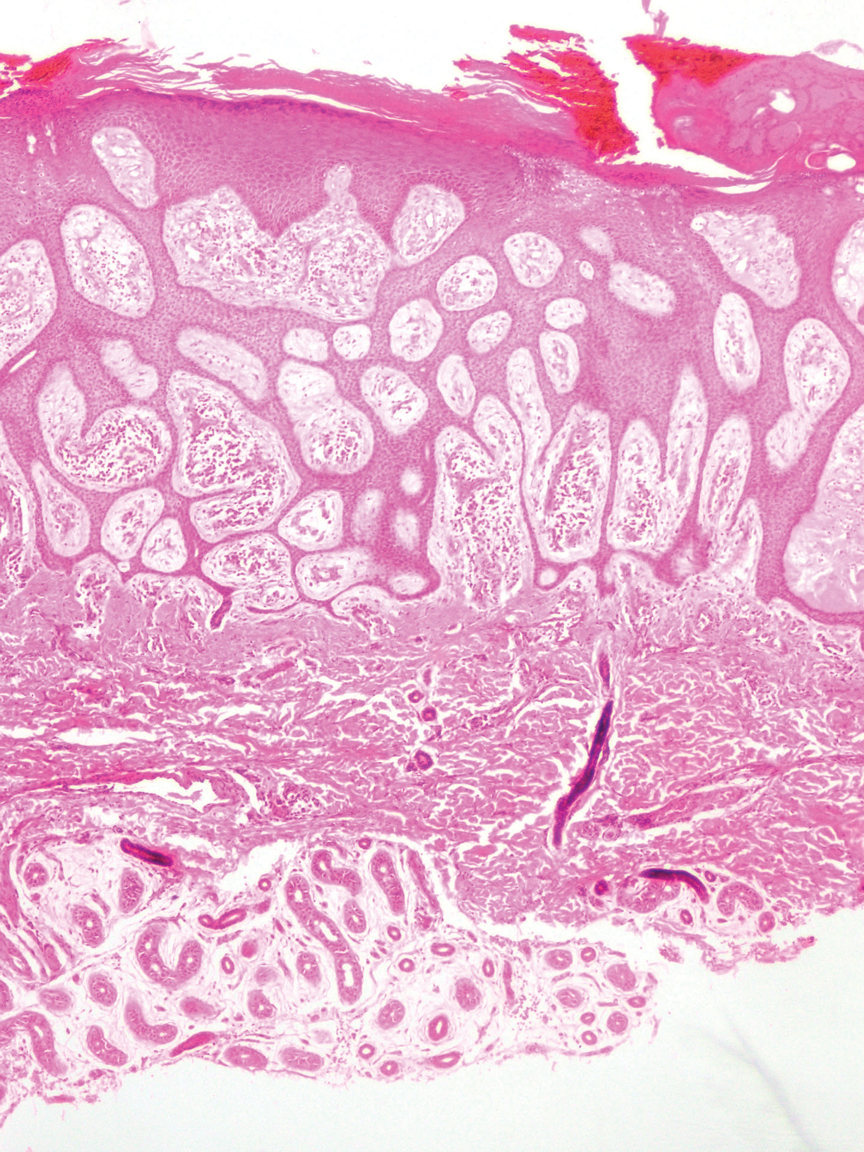

Histopathology showed collections of epithelioid to sarcoidal granulomas throughout the dermis and clustered around nerve bundles with a grenz zone at the dermoepidermal junction. Fite stain was positive for acid-fast bacteria, which were confirmed to be Mycobacterium leprae by by the National Hansen’s Disease program. Based on these findings, a diagnosis of lepromatous leprosy (LL) was made. The patient was treated by the infectious disease department with multidrug therapy that included monthly rifampin, moxifloxacin, and minocycline; weekly methotrexate with daily folic acid; and an extended prednisone taper with prophylactic cholecalciferol.

Lepromatous leprosy transmission is not fully understood but is thought to occur via airborne droplets from coughing/sneezing and nasal secretions.2 Histopathology generally shows a dense and diffuse granulomatous infiltrate that involves the dermis but is separated from the epidermis by a zone of collagen (grenz zone).3 Histology is characterized by the presence of lymphocytes and numerous foamy macrophages (lepra or Virchow cells) containing M leprae organisms. In persistent lesions, the high density of uncleared bacilli forms spherical cytoplasmic clumps known as globi within enlarged foamy histiocytes (Figure 1).4 The macrophages form granulomatous lesions in the skin and around nerve bundles, resulting in tissue damage and decreased sensation. The current standard of care for LL is a multidrug combination of dapsone, rifampin, and clofazimine. Early diagnosis and complete treatment of LL is crucial, as this approach typically leads to complete cure of the disease.